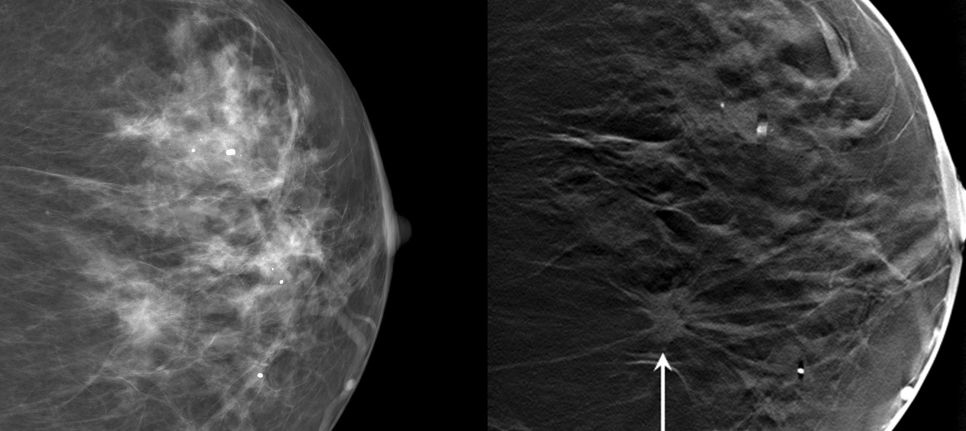

Researchers and biotech companies striving to reduce overtreatment and overdiagnosis come out with new screening tools all the time. But before they make their way into local hospitals, those tools need to be vetted by experts to ensure that the technology offers demonstrable benefits to patients. Tomography, which produces 3D images of the breast in addition to a conventional mammogram, is one such tool. Initial studies indicate that it’s pretty useful—it produces sensitive images that can reduce the number of patients who are called back for additional screening, saving doctors time and reducing patient anxiety. But researchers are still debating tomography’s benefits in the long term. “We’re figuring out how much better [tomography] might actually be,” Smith says.

Duke Medicine